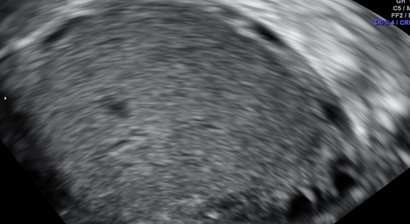

2D, 3D, 4D Ultraschall

Die Ultraschalluntersuchung ist heute von einer kompetenten Frauenarzt-Praxis nicht mehr wegzudenken. Wir verfügen seit 2015 über ein extrem hochwertiges Ultraschallgerät, das neben einer sehr guten Bildauflösung Techniken wie 3D Ultraschall, 4D Ultraschall und verbesserten Doppl...